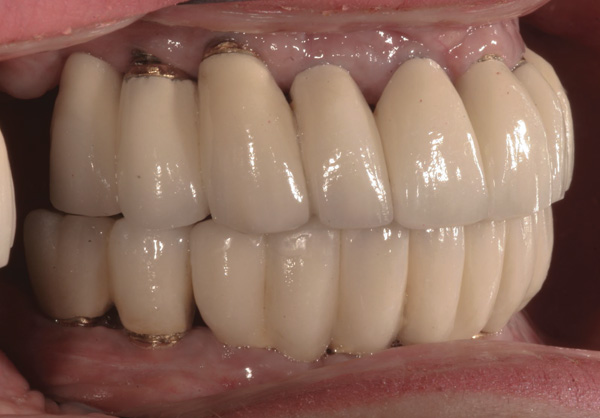

Background: This patient had a failing maxillary dentition and refused to wear a removable prosthesis. A staged approach was employed to retain some of his natural tooth abutments, and recession was noticed at the time of the impression for the second group of implants. Figure 1 shows the patient following insertion of the first set of implant custom abutments; the adjacent natural teeth are still present to support the provisional bridge. Seven months later, as shown in Figure 2, those first-stage custom abutments exhibited evidence of 1 mm to 3 mm of recession.

Results: A decision was made to re-prepare all of the abutments intraorally (Figure 3) so that all abutment margins would be at or below the gingival margin. (Of note, teeth Nos. 8 and 9, also shown in Figure 3, were later submerged for the case to be fully implant-supported.) While re-preparation greatly improved the esthetics of the final result, it required retraction cord placement, new impressions, and new castings.

(Note: A separate but similar type of case shown in Figure 4 and Figure 5 further illustrates intraoral abutment re-preparation.)

Figure 3 Abutments re-prepared intraorally.

Figure 3